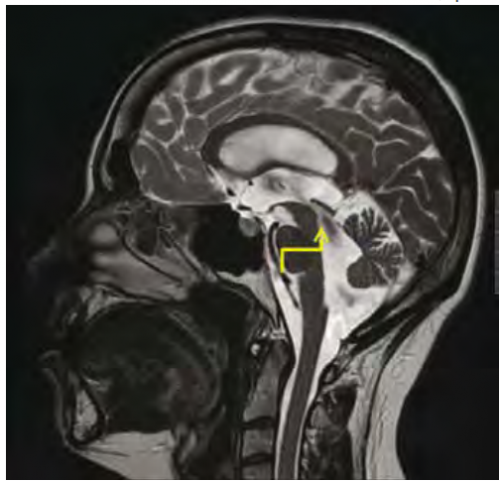

תמונה 1. טומוגרפיה ממחושבת של נבדק עם חשד ל-NPH

Evans Index הינו היחס בין רוחב הקרניים הפרונטאליות לרוחבו המקסימלי של המח. הרחבת חדרים נחשבת Evans Index בגודל 0.3 או יותר במקרה לעיל Evans Index נמדד כ-0.37, מדד המחשיד להגדלת חדרים